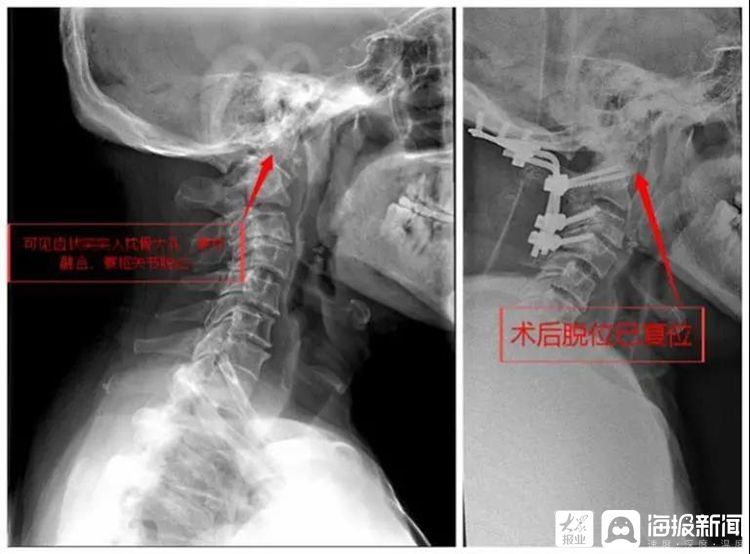

手术前后X线对比